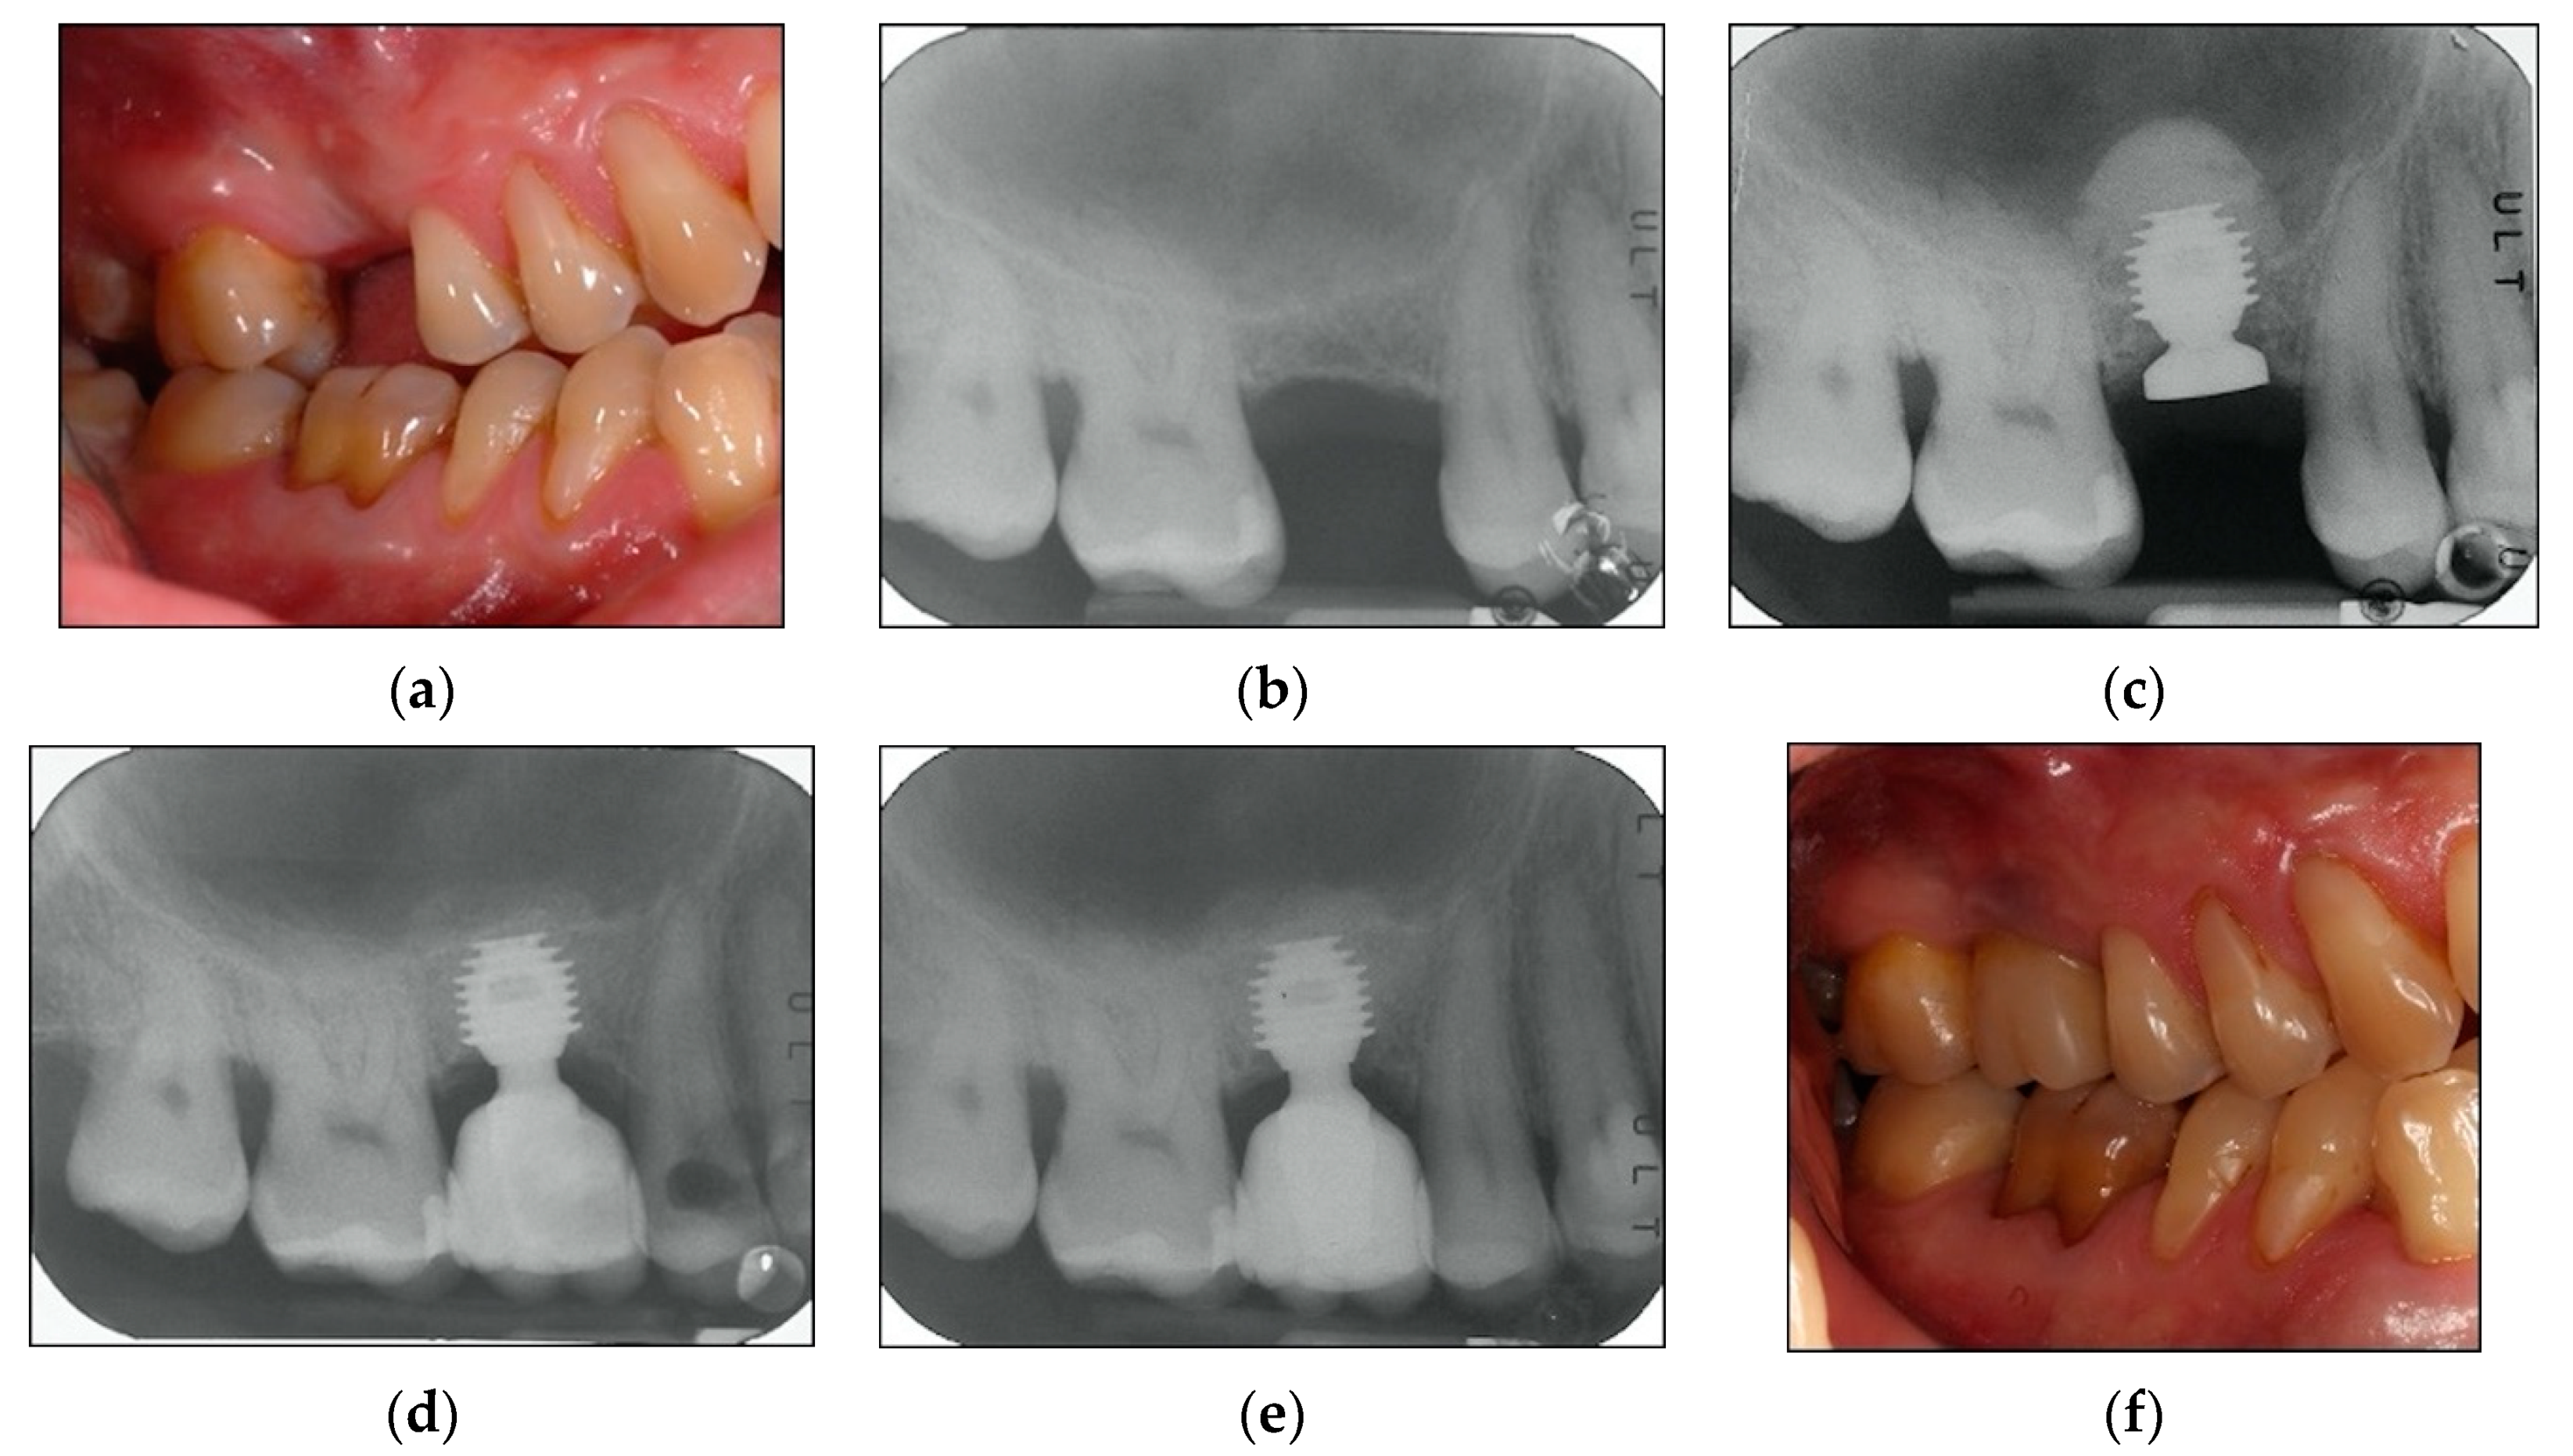

2.2. Surgical Protocol

2.3. Prosthetic Protocol and Follow-Up Evaluation